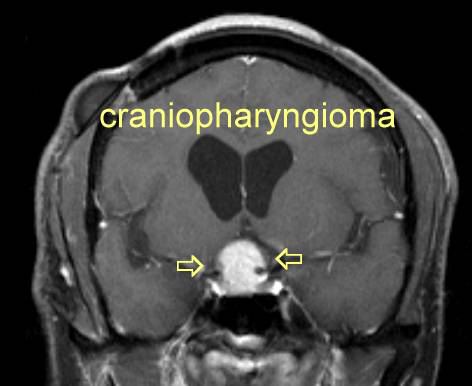

INC旗下国际神经外科顾问团(WANG)专家成员James T. Rutka教授在论文中表示:了解鞍区和鞍上区解剖是选择颅咽管瘤较好手术入路的关键...

颅内颈动脉位于视神经的外侧。颈动脉常突出于蝶窦外侧壁,视神经管突出于蝶窦上外侧,三叉神经二分支突出于蝶窦下外侧。视神经、动眼神经、颈动脉...

颅咽管瘤 是起源于神经上皮的肿瘤,由鳞状细胞沿原颅咽管道长出。它们的发病率在每10万人年0.5至2.5之间,不因性别或种族而有所不同。颅咽管瘤占全部...

儿童颅咽管瘤是一种少见的、鞍区或鞍旁区胚胎性畸形的低级别组织学恶性肿瘤。由于颅咽管瘤与视交叉、脑垂体和下丘脑在解剖学上的邻近关系,其不良...

颅咽管瘤是由鞍区或鞍上区Rathke囊的残余细胞形成的肿瘤,具有囊性和实型成分。虽然它们是良性的,WHO为I级,但由于该病难以治愈,使得它们的生长行为...

颅咽管瘤是一种良性肿瘤(肿瘤),来自于鞍区及其周围(鞍旁区域)的胚胎组织。蝶鞍区位于颅底的中央,主要包括垂体,人体的主腺和蝶鞍,颅骨中的...